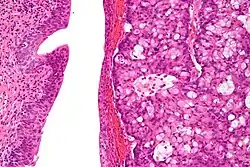

The urachus is also subject to neoplasia. Urachal adenocarcinoma is histologically similar to adenocarcinoma of the bowel. Rarely, urachus carcinomas can metastasise to other regions of the body, including pelvic bones and the lung.[7]